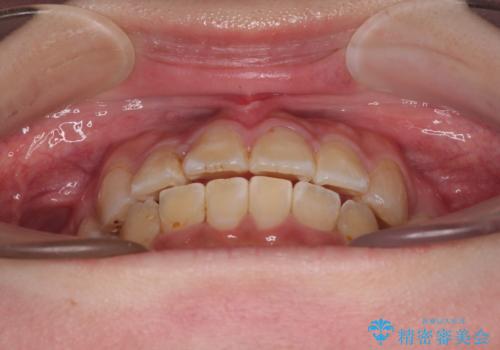

転位歯や埋伏歯などの難易度の高い抜歯矯正治療

- 八重歯や埋伏している奥歯など、多くの難しい問題を抱えている患者様です。

重度叢生のため、大臼歯をしっかりと咬合させるために、下顎は左右第二小臼歯を、上顎は前歯部の叢生を解消するために左右第一小臼歯を抜歯し、口元の突出感を改善するために、上顎大臼歯が前方に移動しないようにするために、補助装置による架強固定を行うこととしました。

叢生は思ったよりも早期に改善されましたが、舌の突出癖による上下前歯の非接触が全く改善されず、2年間ほど治療期間が延びる結果となってしまいました。